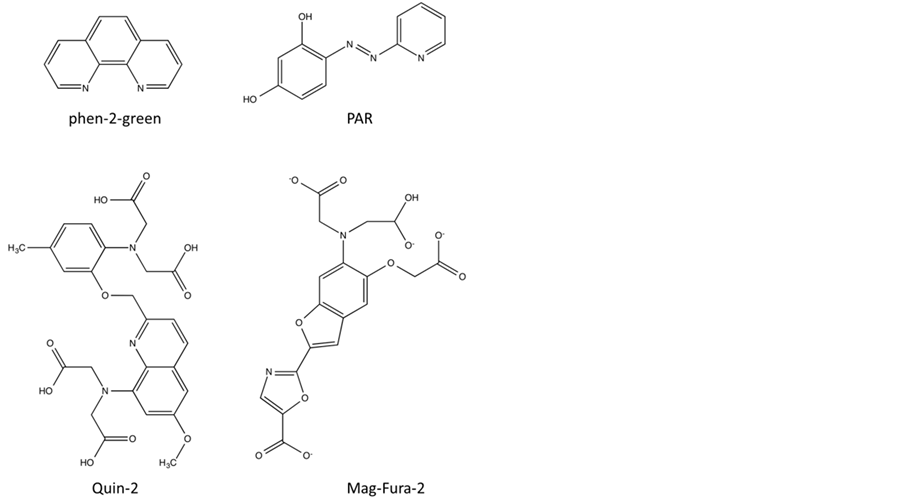

particular transition metal ions, frequently used compounds with convenient colorimetric and fluorimetric prop-

erties are 4-(2-pyridylazo) resorcinol (PAR) and 2-[6-[bis(carboxymethyl)amino]-5(carboxymethoxy)-2-benzof- uranyl], abbreviated here to Mag-Fura, respectively (Figure 7); both compounds have high affinities for Co(II), Ni(II), Cu(II), Zn(II) and Cd(II) [101] -[105] . For a detailed description of the data analysis refer to published literature [18] [60] [106] [107] . A competition assay using Mag-Fura as chelator was employed in order to estimate the binding constants of Zn(II) and Cd(II) to the active site in the B1-type MBL BcII, including several mutants of this enzyme (i.e. H86S, H88S and H149S, point mutations in the Zn1 site, and D90N, C168S and H210S, point mutations in the Zn2 site) [60] . Two binding events are observed, characterised by Kd1 and Kd2; relevant values are summarised in Table 2, and indicate that (a) the affinity of different metal ions for a particular site varies significantly and (b) the two metal ion binding sites also display a large difference in metal ion affinity (note that the binding affinities of Co(II), which were determined spectrophotmetrically by recording the UV-Vis spectrum of BcII as a function of increasing Co(II) concentrations, were included for comparative purposes). For example, in the wild-type enzyme the estimated Kd value of Zn(II) to the tighter binding site (i.e. Kd1) is ~0.6 nM, but only 1.5 µM to the weaker site (i.e. Kd2). Similar values were obtained in competition assays using PAR instead of Mag-Fura [108] . Zn(II) is clearly the preferred metal ion for both binding sites, followed by Cd(II) and Co(II), although catalytic activity can be reconstituted with each of these metal ions [60] .

Figure 7. Chemical structures for PAR, Mag-Fura-2, quin-2 and phen-2-green.

pretation raises a serious issue in terms of why all known MBLs have two closely spaced metal ion binding sites in their catalytic centres-as already mentioned in a previous report it appears unlikely that such a structural arrangement would be conserved throughout evolution if there was no functional benefit for the enzyme [110] . It should also be noted that the binuclear form of BcII is at least twice as reactive as its mononuclear counterpart, and that the Kd values of Zn(II), especially that for the tighter site, may not be as low as estimated by the abovementioned competition-based assays. Using equilibrium dialysis [108] or catalytic activity measurements as a function of Zn(II) concentration [18] Kd1 values of ~0.3 µM and 0.66 µM, and Kd2 values of ~3 µM and 890 µM, respectively, were recorded. To complicate matters further, using isothermal titration calorimetry (ITC) only one binding event was observed when metal ion-free BcII was titrated with Zn(II). Since the associated stoichiometry was, however, close to 2 it was suggested that two Zn(II) ions with comparable affinities (with an estimated Kd value of ~30 µM) are bound to the enzyme [111] . Similar metal ion affinities for the two binding sites were also recorded for the B1-type MBL Ccr from Bacteroides fragilis with estimated Kd values ≤ 10 µM [97] ; only the binuclear enzyme is believed to be active [98] . In a more recent study with BcII the competition assay using Mag-Fura as chelator was repeated as part of an extended study to investigate the process of Zn(II) binding in this enzyme [109] . The authors concluded that metal ion binding is a positively cooperative process and estimated metal ion affinities similar to the values reported by Badarau and Page, using ITC [111] . The reason for the largely differing Kd values obtained from competition-based assays remains unclear, but it appears increasingly likely that the binuclear form of the B1-type MBLs (and likely also the B3-type MBLs) is the physiologically relevant one [74] , especially since extracellular Zn(II) concentration may be significantly larger than within cells. While in B1- and possibly also B3-type MBLs the binding of a second metal ion is driven by positive cooperativity and leads to an increase in reactivity, in B2-type MBLs it leads to inhibition (with a Ki of ~50 µM) [71] . Metal ion affinity constants for the B2-type MBL CphA from A. hydrophila were also estimated in competition experiments using quin-2 as chelator for Zn(II) and Cd(II), and phen-green for Cu(II) (Figure 7). Co(II) affinities were estimated spectrophotmetrically by recording the UV-Vis spectrum of CphA as a function of increasing Co(II) concentrations [19] . Kd values ranged from the low picomolar range for Zn(II) to ~600 nM for Cu(II) for the tighter metal ion site to micromolar range for the weaker one. These values are of a similar magnitude as those reported for the B1-type MBL BcII (see above).